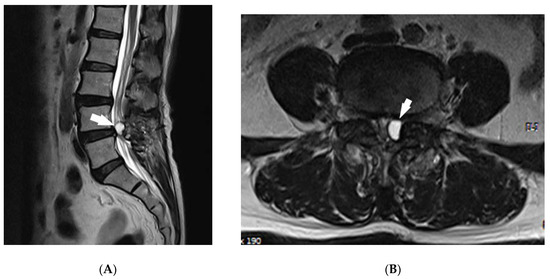

Background: Synovial cysts rarely occur after a laminectomy and are difficult to detect if there are no symptoms; however, they can cause lower back pain or symptoms of radiculopathy. Various methods are used to treat synovial cysts. Here, we will introduce the [...] Read more.

Background: Synovial cysts rarely occur after a laminectomy and are difficult to detect if there are no symptoms; however, they can cause lower back pain or symptoms of radiculopathy. Various methods are used to treat synovial cysts. Here, we will introduce the first case with treatment using the transforaminal epiduroscopic laser annuloplasty (TELA) system. Case report: A 64-year-old female patient visited the pain clinic with lower back pain and pain radiating from the left lower extremity. An MRI T2 image showed a synovial cyst of facet joint origin at the L4–L5 level; the patient had undergone a laminectomy 10 years ago at the same spinal level. The patient rated the pain an 8 on the numerical rating scale (NRS), and pain was reduced after epidural steroid injection, but symptoms recurred a month later. The cyst ablation was performed using the TELA system with a 1414 nm neodymium-doped yttrium-aluminum-garnet (Nd:YAG) laser, and after the procedure, pain decreased to 4 points immediately and was reduced to 2 points on the NRS after 1 week. Six months after the procedure, the pain level was measured on NRS 2 and cyst was not recurred in the additional MRI. Conclusion: We introduced the TELA system as a noninvasive therapy for treating synovial cysts. Ablation of cystic necks using a 1414 nm Nd:YAG laser could be a method to prevent cyst recurrence, but long-term follow-up and large scale control studies will be needed to verify the effectiveness of this method. Full article